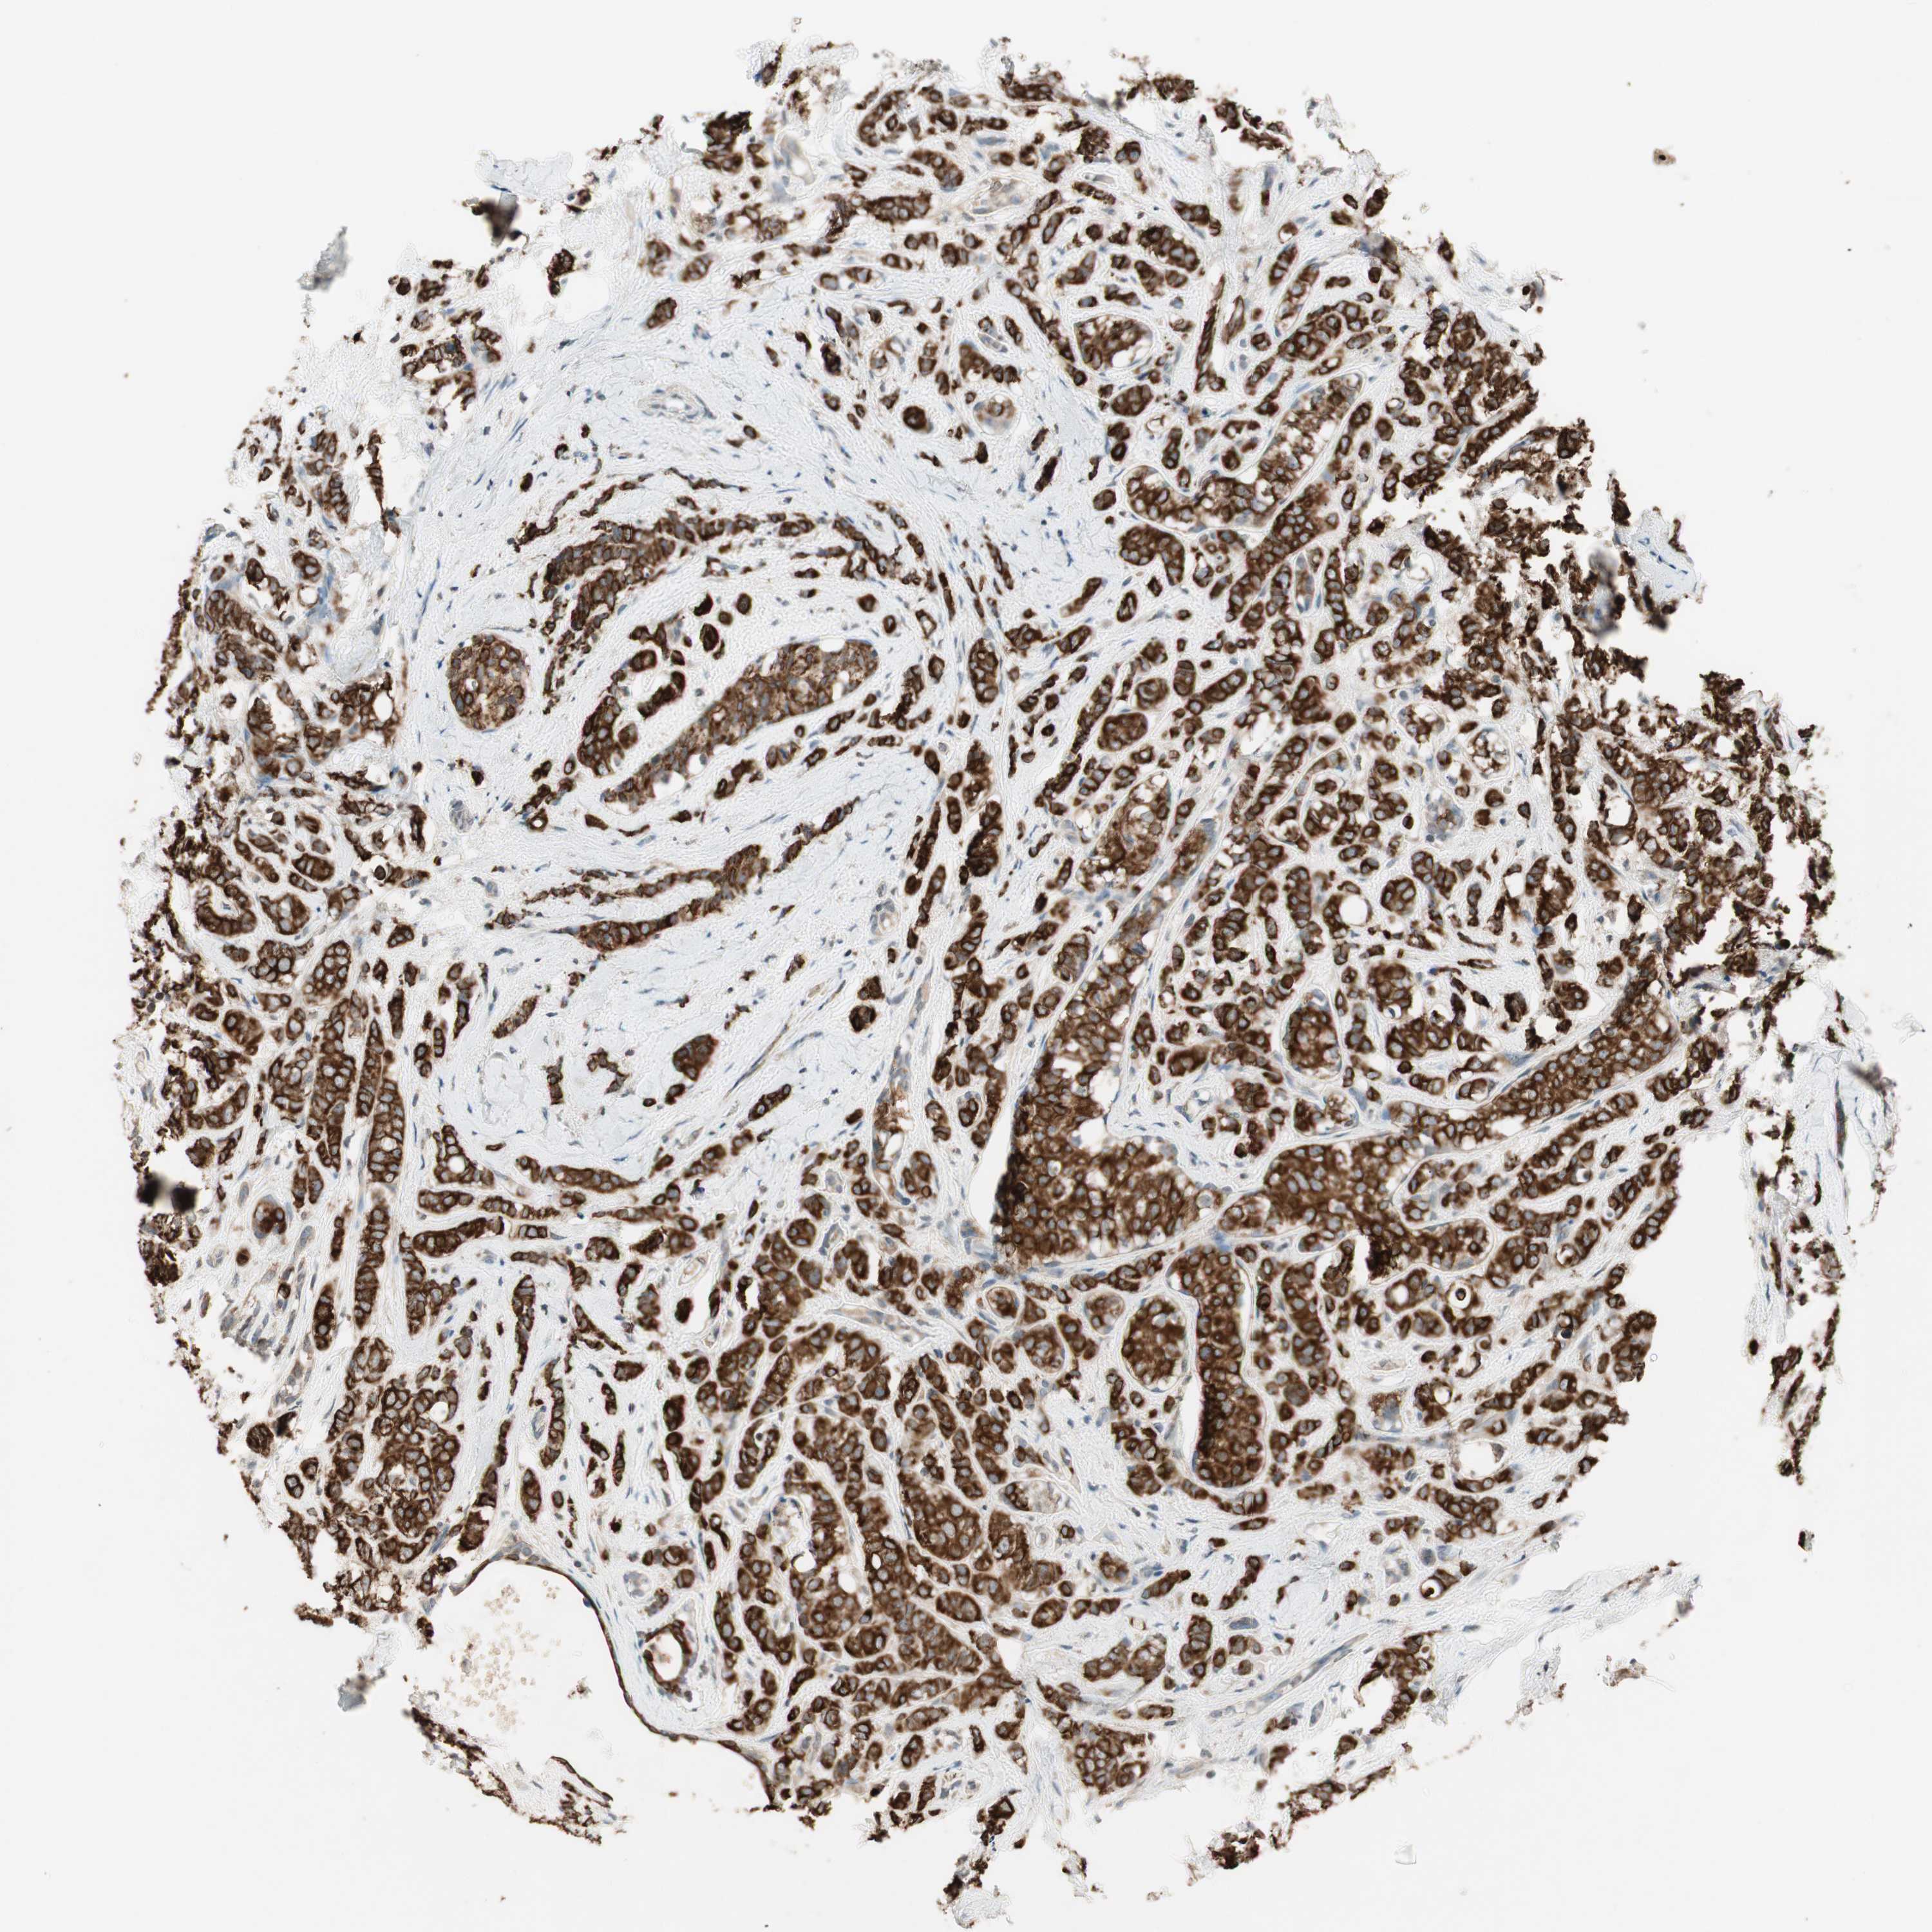

BRCA TCGA BRCA VALIDATION PROTEIN EXPRESSION

ANTIBODIES

AND

VALIDATION